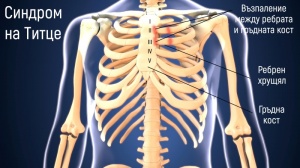

Синдром на аортната дъга [Takayasu]

Синдром на аортната дъга, известен още като артериит на Текаясу, е системно възпалително заболяване, което води до увреждане на средните и големите артерии и техните клонове. Среща се предимно при млади жени от азиатски произход. Обикновено е засегната ао